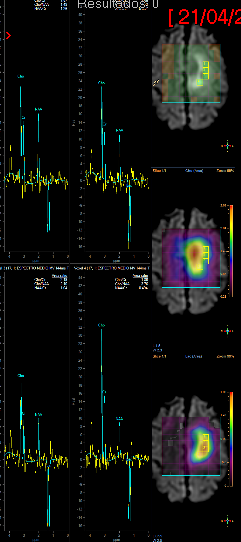

Fig3a,b – Espectroscopia de Múltiplos Voxels (EMV) em caso de glioma de alto grau (Astrocitoma anaplásico – III) frontal esquerdo. Traçados de mini voxels colocados no interior e no tecido cerebral vizinho (a, b), para avaliar grau de invasividade tumoral mostram níveis elevados de cholina dentro e fora da lesão.

Fig3c,d – Espectroscopia de Múltiplos Voxels (EMV) em caso de glioma de alto grau (Astrocitoma anaplásico – III) frontal para sagital esquerdo. Traçados de mini voxels colocados no interior e no tecido cerebral vizinho para avaliar grau de invasividade tumoral mostram níveis elevados de cholina dentro e fora da lesão redução do NAA (c) e acúmulo de lactato(d).

A figura acima apresenta mapa de metabólitos (cholina e NAA) que mostram redução de NAA por substituição de tecido normal por células neoplásicas e acúmulo de cholina por proliferação celular glial (c). Também o mapa de metabólitos (cholina e lactato), mostra, além de acúmulo de cholina, a presença de lactato, inferindo hipóxia intratumoral (d).